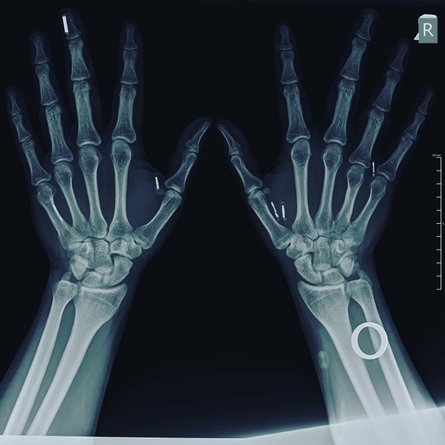

Павло Кльоц, мікрочіп в руці, мікрочіпи на рентгені

У тілі чоловіка вісім мікросистем